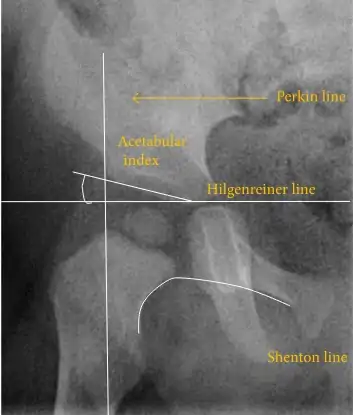

The most useful lines and angles that can be drawn in the pediatric pelvis assessing hip dysplasia are as follows:[45] Different measurements are used in adults.[45]